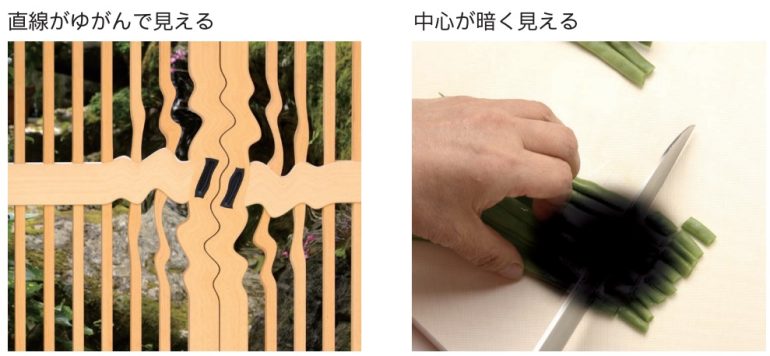

視野のゆがみ、中心暗点、視力低下、コントラスト低下といった症状をきたし、見え方が低下します。現在、加齢黄斑変性は、国内の視覚障害者手帳交付の原因疾患において第4位にある病気です。すでに欧米先進国では成人(特に50歳以上)の中途失明の主要原因疾患になっており、生活習慣の欧米化が進む日本でも、加齢黄斑変性の患者数は増加傾向にあります。

中心暗点

見たい部分が黒くなって見えます。